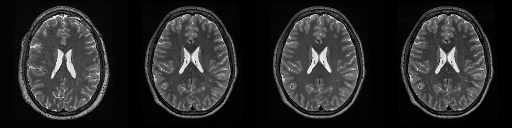

HCP T2w dataset

We utilize images from the publicly available Human Connectome Project (HCP) [51] T2-weighted (T2w) images dataset for the task of compressed sensing, which contains brain images from 47 patients. The HCP dataset includes cross-sectional images of the brain taken at different levels and angles.

Compressed sensing

We train a flow-based model from scratch on 10,000 randomly sampled images, utilizing the ncsnpp architecture [9] with minor adaptations for grayscale images. We employ compression rates , meaning . The measurement operator is given by a subsampled Fourier matrix, whose sign patterns are randomly selected. We evaluate our reconstruction algorithm’s performance on 200 randomly sampled test images.

We present the quantitative and qualitative results of compressed sensing in Tab. 1 and Fig. 4, respectively. As shown in Tab. 1, our method consistently achieves the best performance across varying compression rates . In Fig. 4, our method produces reconstructions that are more faithful to the original images, with fewer artifacts, leading to higher accuracy and clearer details.